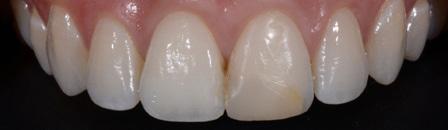

Class IV controlled layer concept utilising G-ænial™ A’CHORD in 3 shades

This case study presents the clinical management of a patient who presented with an existing failed anterior composite, requiring a Class IV direct composite replacement. The restoration aimed to achieve seamless integration with the natural dentition while restoring form and function.

Figure 1 - Pre-Operative presentation, exhibiting a failed direct composite restoration on the upper left central incisor (Tooth 21).

Figure 7 – 2-week review demonstrating the complete optical and functional G-ænial™ A’CHORD restoration on the tooth 21.